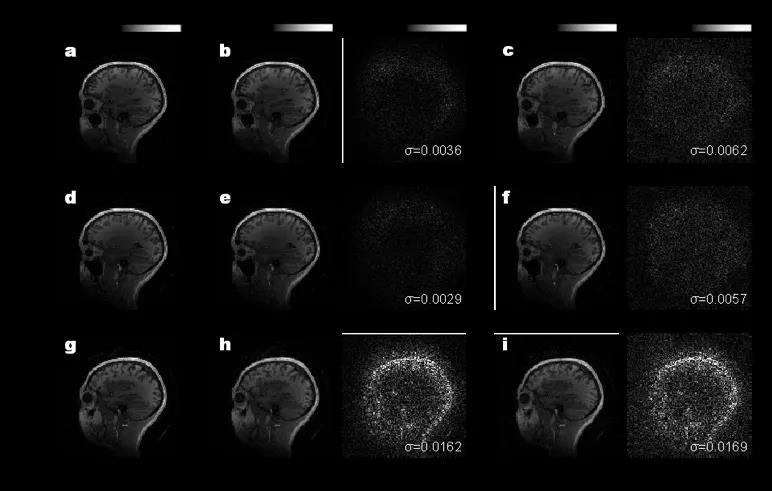

本研究中,邹卫文教授团队利用医学图像重构任务作为验证,在芯片上成功地运行了AUTOMAP(用于通用图像重构)神经网络模型,图像重构的质量接近了32位计算机的理想水平。该工作不仅推动光学神经网络研究领域攻克实际应用难题,更为下一代智能计算技术提供了新思路。后续进一步提高芯片的器件集成规模,有望实现更高速、更低功耗的光学神经网络处理器,缓解智能算力需求剧增与传统硬件算力受限的矛盾。